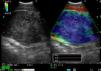

A 74-year-old male smoker with hypertension, dyslipidemia, previous acute myocardial infarction and polycythemia. He reported a 45-day history of progressive dysphonia and a sensation of instability for 3–4 months that had intensified in the previous few days, to the stage that he could no longer stand. The chest CT showed a pulmonary nodule measuring 2cm in the right upper lobe, suggestive of primary pulmonary neoplasia, multiple small bilateral pulmonary nodules suggestive of metastasis, and multiple enlarged mediastinal lymph nodes. A head CT revealed radiological signs indicative of multiple cerebral metastases. Due to significant cerebral edema,6 ultrasound-guided bronchoscopy with esophageal access was performed under conscious sedation with midazolam. A 20mm subcarinal lymphadenopathy was visualized and aspirated. Elastography mode indicated that the consistency of this nodule was significantly increased (Fig. 2). The diagnosis was metastatic lung adenocarcinoma.